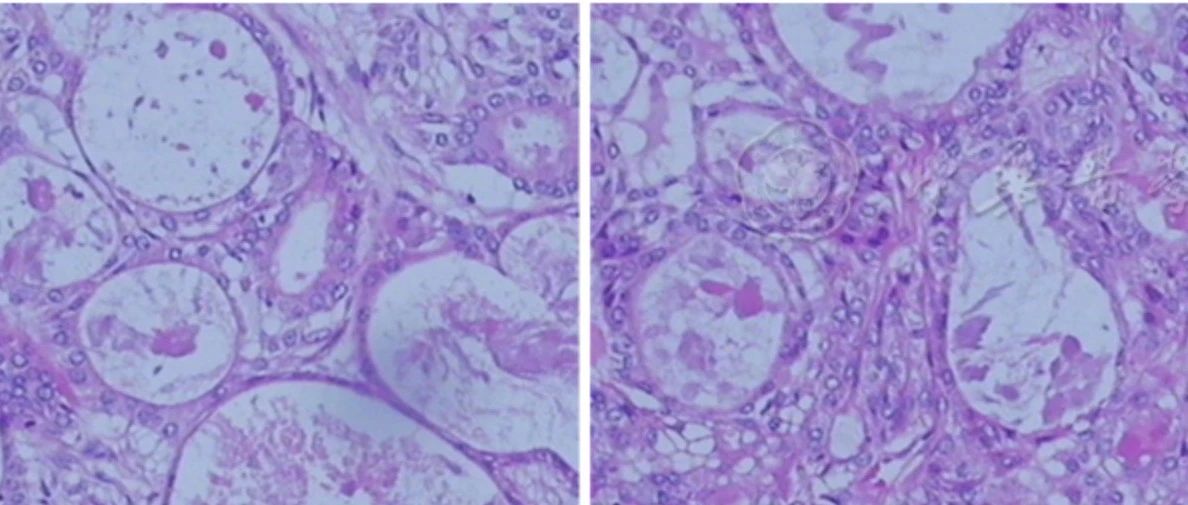

儿童肺黏液表皮样癌6例

汪凤华, 梁建华, 李乐, 等.  儿童肺黏液表皮样癌6例 [J] . 中华肿瘤杂志, 2022, 44(9) : 987-989. DOI: 10.3760/cma.j.cn112152-20200917-00830.黏液表皮样癌是常发生于涎腺、泪腺等部位的恶性肿瘤,而原发于肺及支气管者少见,约占肺癌的0.1%~0.2%[1]。肺黏液表皮样癌(pulmonary mucoepidermoid carcinoma, PMEC)的发病年龄跨度较大,3~78岁均可发生,但大多数发生于30~40岁患者,儿童发病非常少...